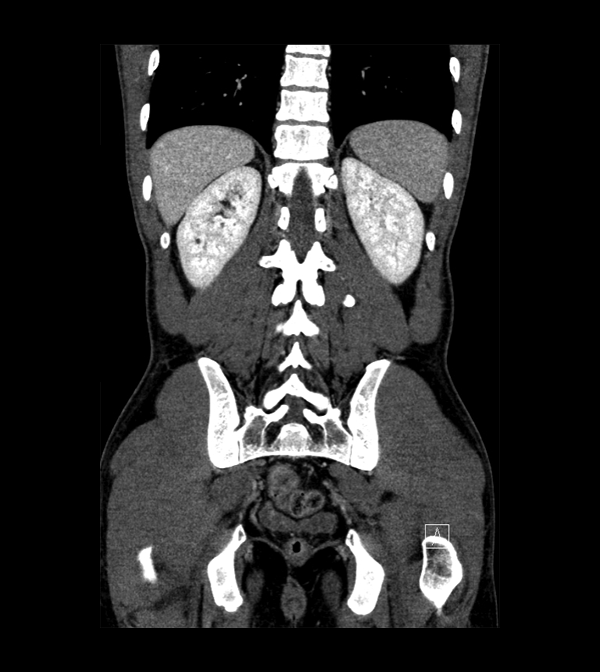

Body

Covers abdominal CT anatomy.